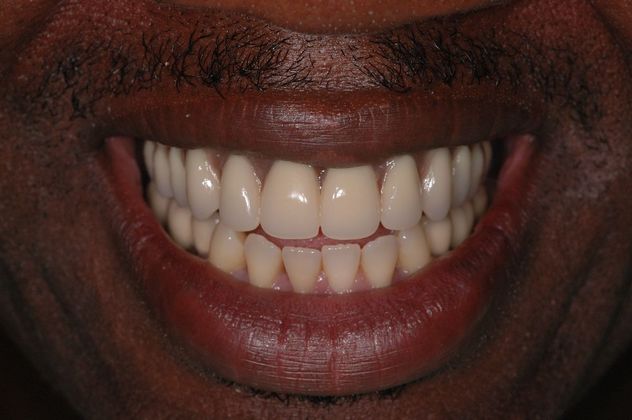

This young man had an early onset of periodontal disease (gum disease) causing him to have all loose upper teeth and loose lower back teeth, all of which needed to be removed. After that, 6 implants were placed in the upper jaw for the All-on-6 bridge and 4 implants were placed in the lower jaw for bridges for back side of the mouth. The lower front natural teeth were cleaned off disease and maintained.

Procedures : extractions, implants, All on 6, Teeth in a day, bite correction.

Testimonial : "I have complete trust in Dr. Bidra who gave me back my smile, my confidence and my ability to chew and speak in the quickest possible manner. I would not open my mouth for treatment for anyone else other than Dr. Bidra"